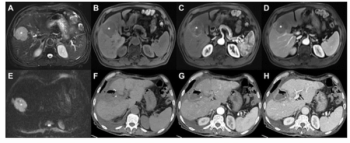

Emphasizing factors such as tumor size, serum neutrophil count and arterial phase hyperenhancement proportion on MRI, a new diagnostic model outperformed eight staging systems for predicting advanced recurrence of hepatocellular carcinoma after liver resection.